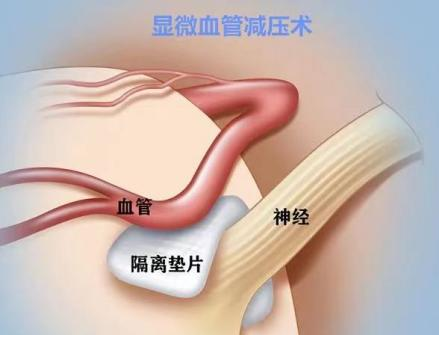

微血管减压术

微血管减压术 |

微创、安全、有效率95%,术后不产生麻木 |

开颅手术,存在一定手术风险 |